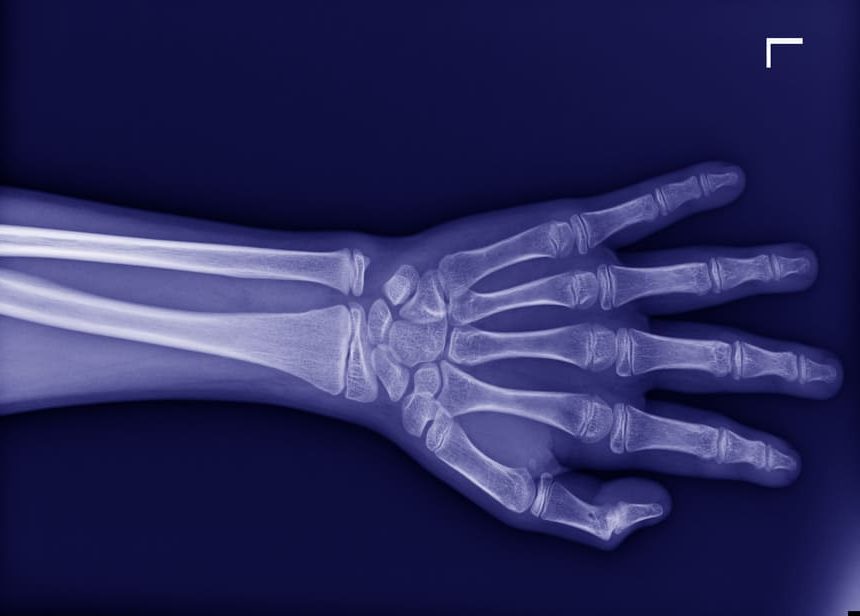

radiographie de la main 2

Thumb Carpometacarpal Osteoarthritis (Rhizarthrosis): When Should Surgery Be Performed?

Decision-making factors for surgical intervention based on pain, functional impairment, and alternative treatments.

radiographie de la main 3

Surgical Treatment of Thumb Carpometacarpal Osteoarthritis: The Role of Trapeziometacarpal Prosthesis

Analysis of the benefits and limitations of trapeziometacarpal prostheses in severe thumb osteoarthritis.

radiographie de la main 1

Dupuytren’s Disease: Rupture of the Flexor Digitorum Profundus Tendon

Study of rare complications of Dupuytren’s disease, including tendon rupture, and surgical options to restore finger mobility.